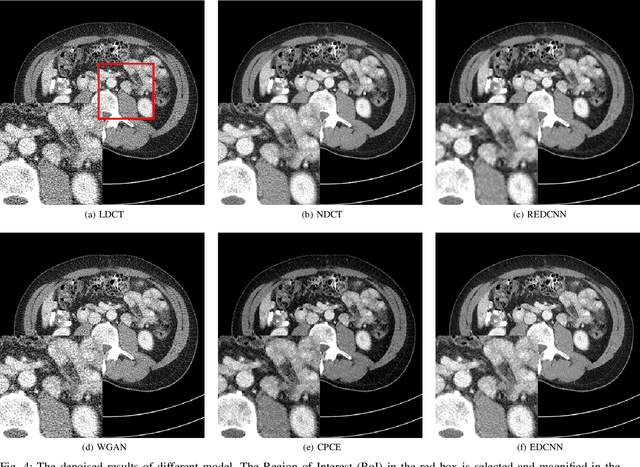

Abstract:In the past few decades, to reduce the risk of X-ray in computed tomography (CT), low-dose CT image denoising has attracted extensive attention from researchers, which has become an important research issue in the field of medical images. In recent years, with the rapid development of deep learning technology, many algorithms have emerged to apply convolutional neural networks to this task, achieving promising results. However, there are still some problems such as low denoising efficiency, over-smoothed result, etc. In this paper, we propose the Edge enhancement based Densely connected Convolutional Neural Network (EDCNN). In our network, we design an edge enhancement module using the proposed novel trainable Sobel convolution. Based on this module, we construct a model with dense connections to fuse the extracted edge information and realize end-to-end image denoising. Besides, when training the model, we introduce a compound loss that combines MSE loss and multi-scales perceptual loss to solve the over-smoothed problem and attain a marked improvement in image quality after denoising. Compared with the existing low-dose CT image denoising algorithms, our proposed model has a better performance in preserving details and suppressing noise.